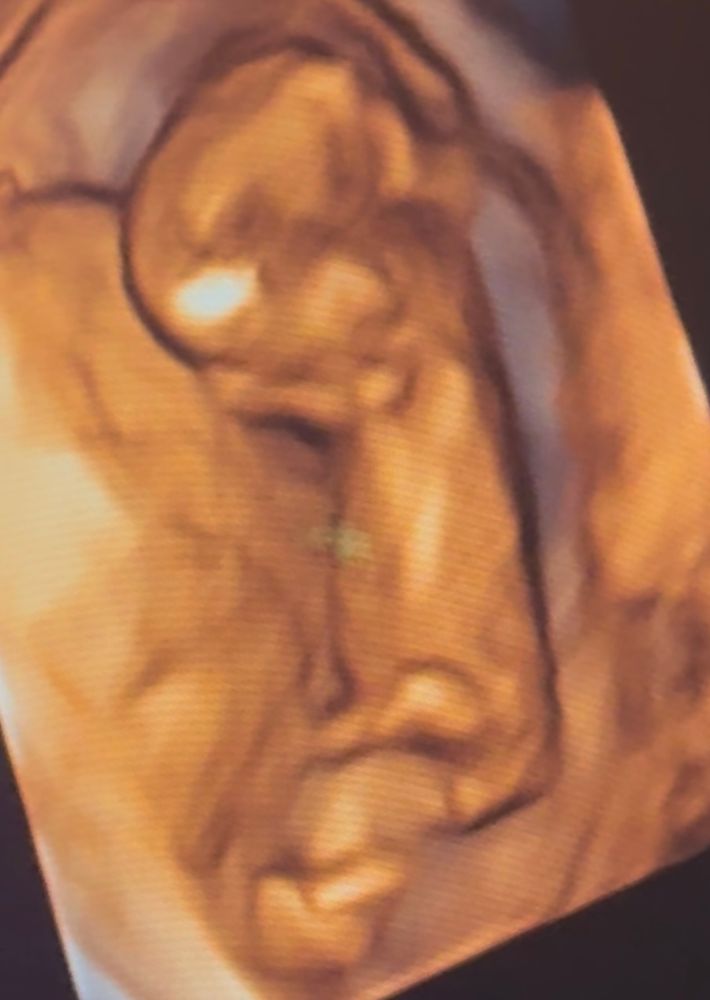

Пол малышаДевушки, кто разбирается, подскажите, пожалуйста, как вы думаете, кто тут мальчик или девочка?) на первом фото бугорок параллельно, на втором будто что-то торчит🫣 Фото сделаны на одном узи, 13 недель и 1 день

В 15 недель подтвердили девочку🥰

Девочка. Половой бугорок параллелен спинке🌸

Девочка) у нас в 11,5 недель четко показало мальчика, половой бугорок был вверх как 90 градусов) 🌸